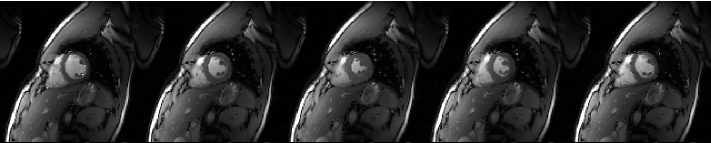

Experiments are conducted on a 2D cardiac MRI dataset acquired on a 3T Siemens Trio scanner using a 32-coil matrix body array. Fully sampled data were acquired using a matrix (FOV = mm) and 22 temporal frames. The fully sampled data is then retrospectively undersampled by a factor of 8 using a different variable density random undersampling along vertical axis for each time point as shown in Figure 1. The data is normalized so that the reconstruction of the fully sampled data leads to images with maximum intensity of 1. The sample frames from reconstruction of the fully sampled data can be seen in Figure 2. The subsampled data is reconstructed with Algorithm 1 and Algorithm 2 using the SVD method to compute the term and setting temporal DFT as and temporal TV as respectively. The same value that results in good quality reconstruction is used for all the tested algorithms ().